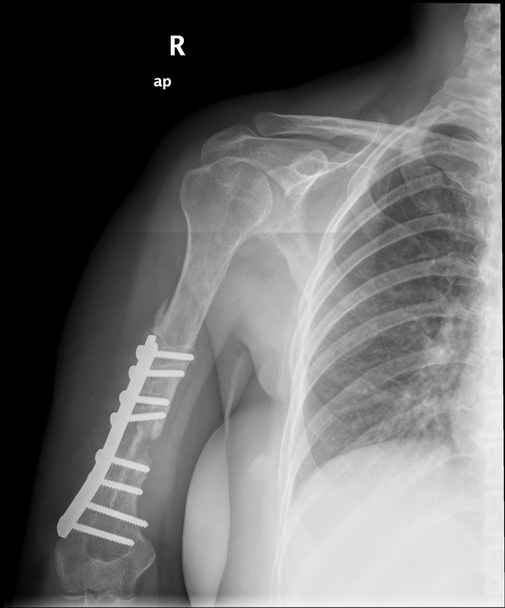

Больная 48 лет, медсестра-массажист, перелом плеча 7 лет назад, оперирована 4-кратно и безуспешно

Больная 48 лет, медсестра. Травма получена 7 лет назад, оперирована первично в Турции - остеосинтез пластиной - несращение - реостеосинтез стержнем там же через год (обычным, с выстоянеием его в полость плеча) - несращение - поступила к нам впервые в марте 2008 года - удаление стержня, реостеосинтез пластиной и костная пластика, в течение 2 лет лизис кости вокруг винтов, смещение фиксатора, в марте 2010 - удаление пластины, реостеосинтез интрамедуллярным стержнем с блокированием (рассверливание + костная пластика). В динамике - вновь лизис в области перелома, нестабильность дистальных блокирующих винтов.